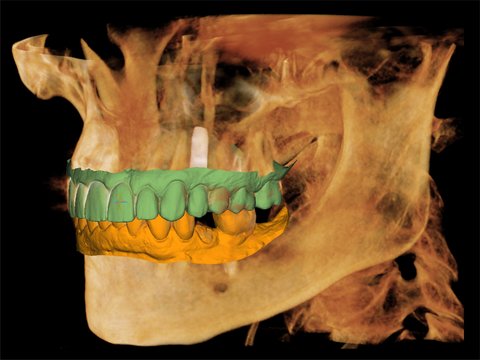

Das Green X ist ein 4-in-1 Röntgenbildgebungssystem der Superlative, welches sowohl 2D-Modalitäten wie Panorama- und kephalometrische Aufnahmen in ultrahochauflösender Bildqualität ermöglicht, als auch flexible 3D-DVT-Aufnahmen von Patienten, Modellen und Abformlöffeln.

• 4-in-1 Digital X-Ray Imaging System Pano / Ceph / DVT / Modellscan

• Multi-FOV-Auswahl für alle dentalen Indikationen 4x4 / 5x5 / 8x5 / 8x8 / 12x9 / 16x9

Die Überlagerung der Oberflächenmodelle (STL-Daten) aus externen Scan-Systemen ist durch die exzellente Oberflächendarstellung der 3D-Röntgenaufnahmen problemlos und komfortabel. Somit bietet das Green X alle Möglichkeiten, den digitalen Workflow im Praxisalltag umzusetzen. Eines für alles und alles für Sie!

3D-Modell-Scan: Ready for CAD/CAM

Integrierter Laborscanner mit automatischer Datenspeicherung im byzznxt Langzeitarchiv

Die integrierte Modell-, Abdruck- und Prothesenscan-Funktion des Green X bietet die Möglichkeit, die zur Fertigung von Bohrschablohnen und Interims-Prothesen, notwendigen Daten zu erfassen. Mit der STL-Konvertierungsfunktion der byzzEz3D-i Software können jederzeit die gewünschten Daten im Standard STL-Format exportiert werden. Zusätzlich werden alle Scandaten im Langzeitarchiv von byzznxt abgespeichert und die Daten stehen somit jederzeit für 3D-Druck oder CAD/ CAM-Verfahren zur Verfügung.